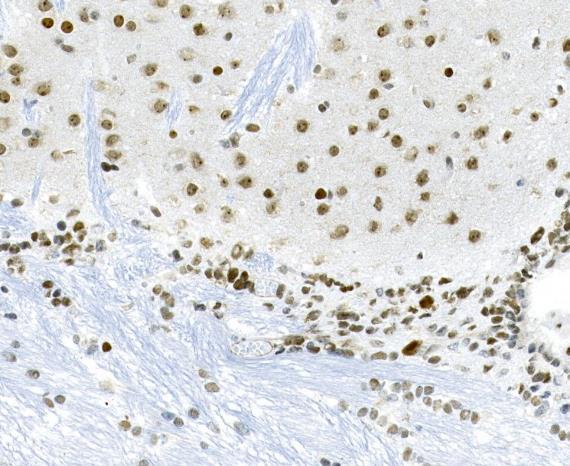

Formalin-fixed;paraffin-embedded mouse brain tissue stained for Tau (Phospho-Ser404) using 14288 at 1/100 dilution in immunohistochemical analysis.